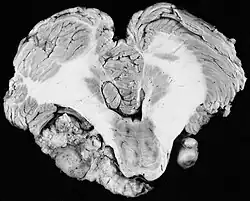

Bilateral schwannomas in a patient with neurofibromatosis type II